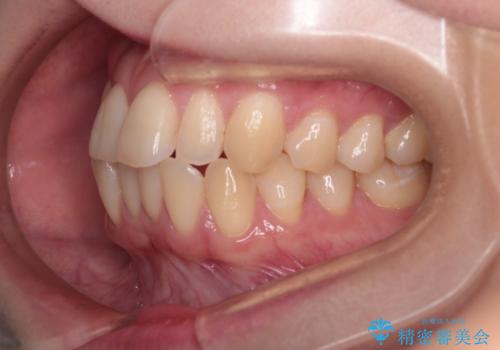

【インビザライン】反対咬合を治したい

- 前歯の反対咬合を主訴に来院されました。

インビザラインにて歯列弓の拡大により叢生の改善を行うことができ、患者様にも満足していただました。

前歯の反対咬合は歯牙への負担も大きくできるだけ早期に治療を行うことを推奨しています。